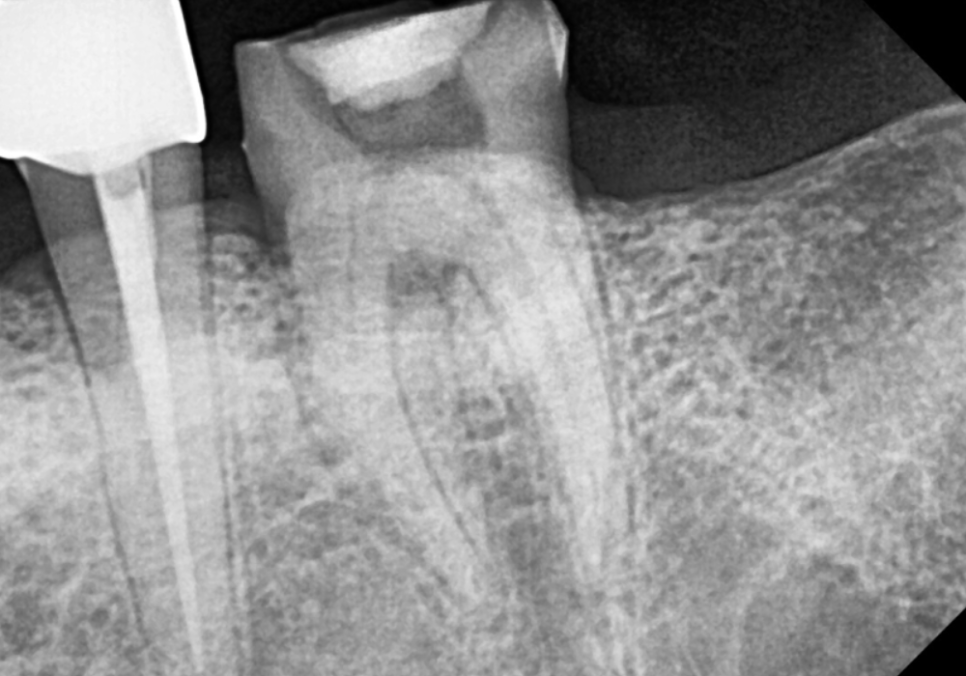

엑스레이와 구강 상태를 꼼꼼히 확인해 보니,

이번 치아는 다행히

발치 없이 충분히 살려서 쓸 수 있는 상태였습니다.

뿌리 쪽 뼈 상태도 염증 없이

깨끗하게 유지될 수 있었습니다.

240812

충치가 있긴 했지만

치아 뿌리는 튼튼했기에,

치아 내부의 오염된 신경관을

청소하는 신경치료를 진행했습니다.